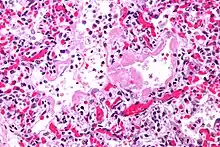

Micrograph of diffuse alveolar damage, the histologic correlate of acute interstitial pneumonitis. H&E stain.

Rapid progression from initial symptoms to respiratory failure is a key feature. An X-ray that shows ARDS is necessary for diagnosis (fluid in the small air sacs (alveoli) in both lungs). In addition, a biopsy of the lung that shows organizing diffuse alveolar damage is required for diagnosis. This type of alveolar damage can be attributed to nonconcentrated and nonlocalized alveoli damage, marked alveolar septal edema with inflammatory cell infiltration, fibroblast proliferation, occasional hyaline membranes, and thickening of the alveolar walls. The septa are lined with atypical, hyperplastic type II pneumocytes, thus leading to the collapse of airspaces. Other diagnostic tests are useful in excluding other similar conditions, but history, X-ray, and biopsy are essential. These other tests may include basic blood work, blood cultures, and bronchoalveolar lavage.